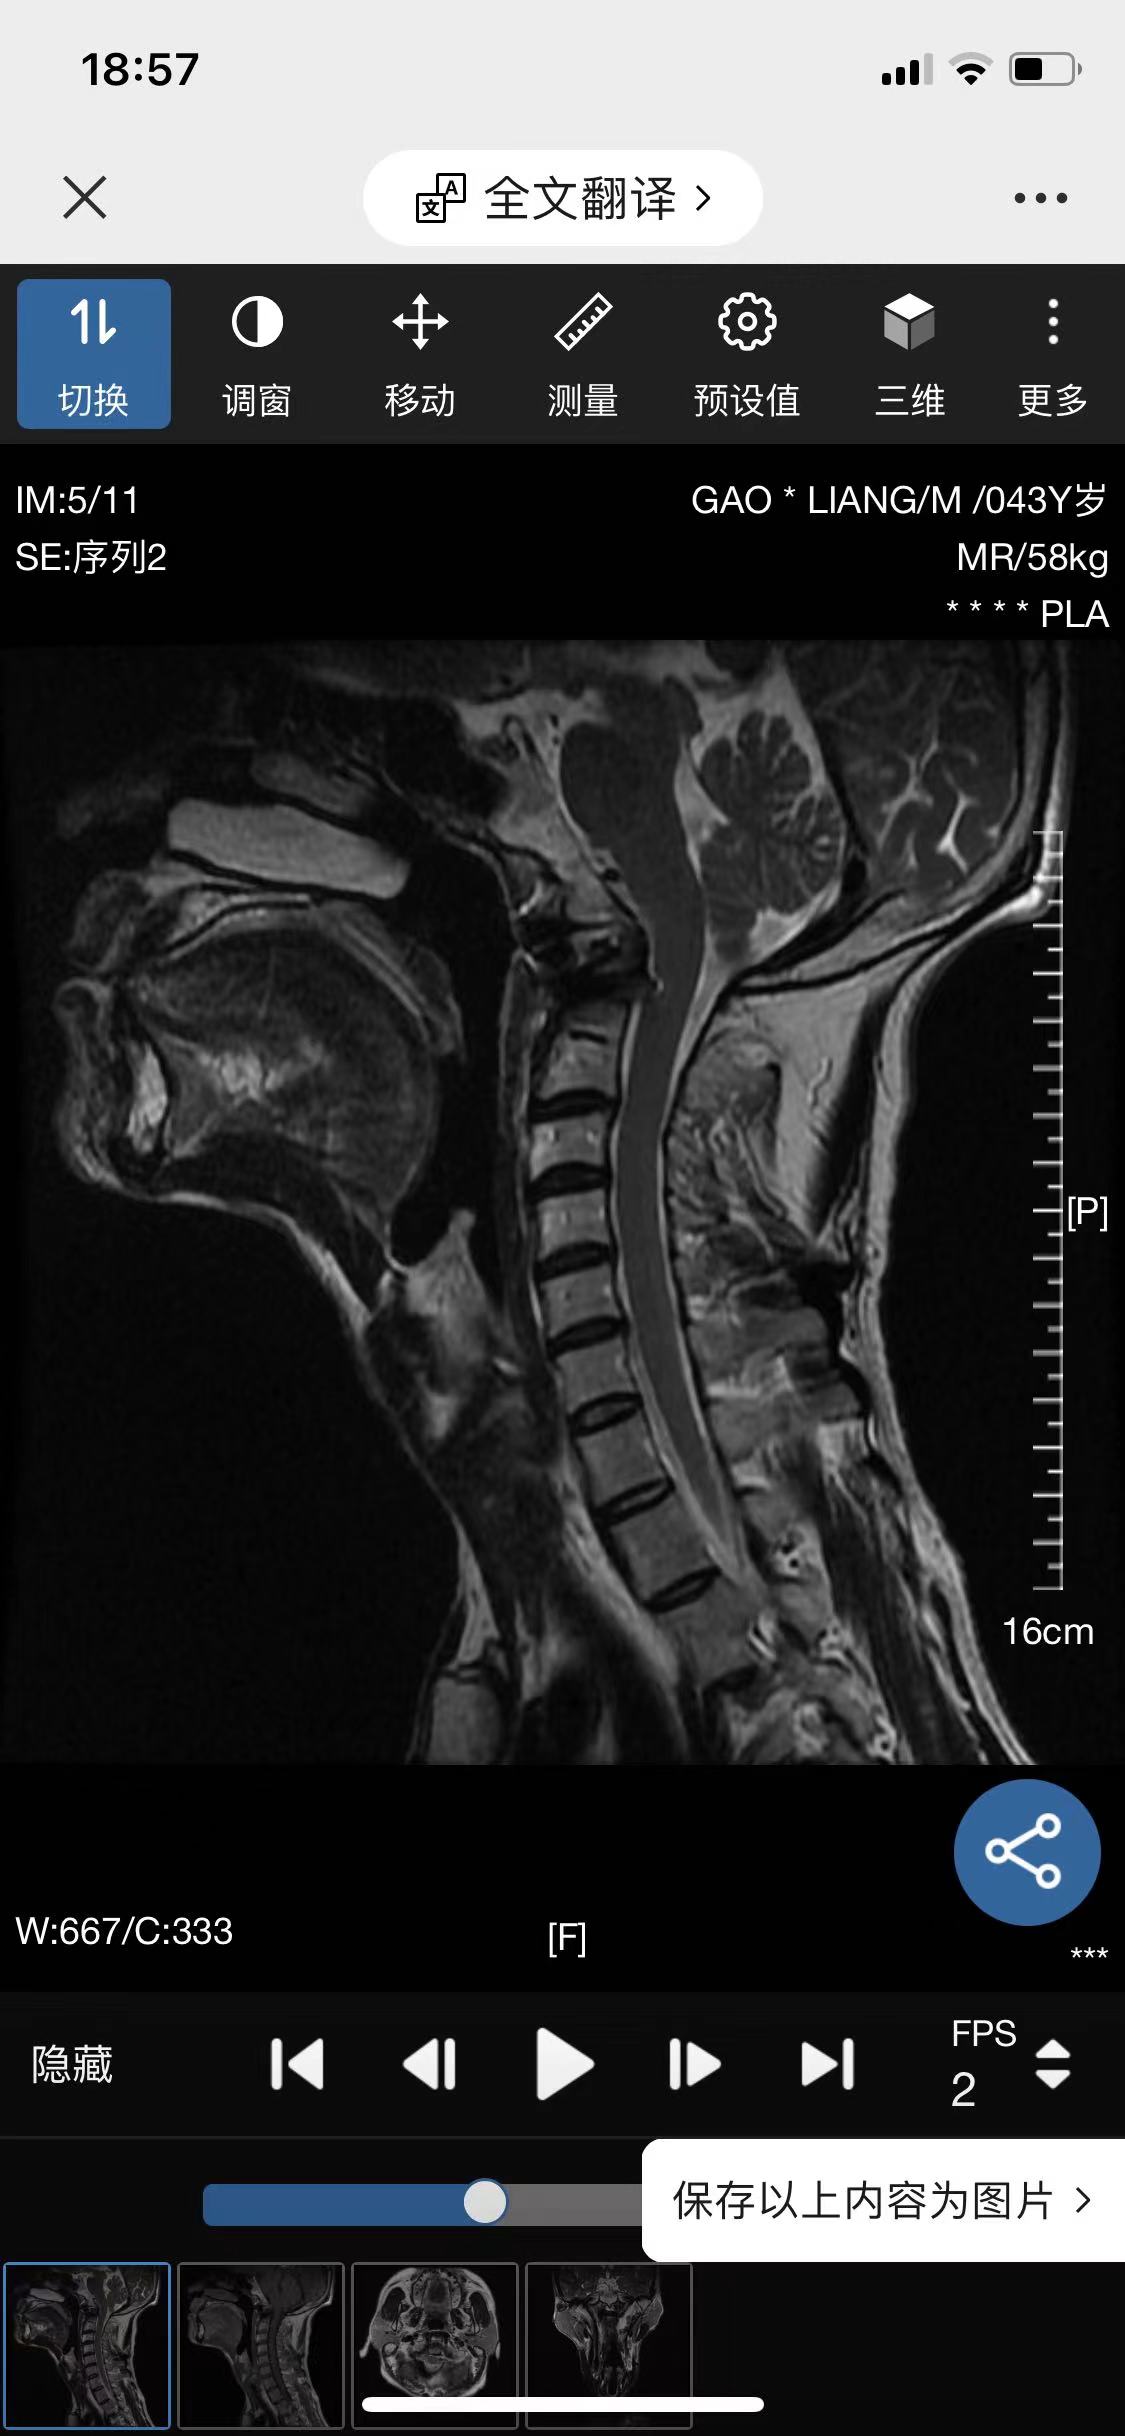

• 诊断:寰枢椎脱位

• 影像: